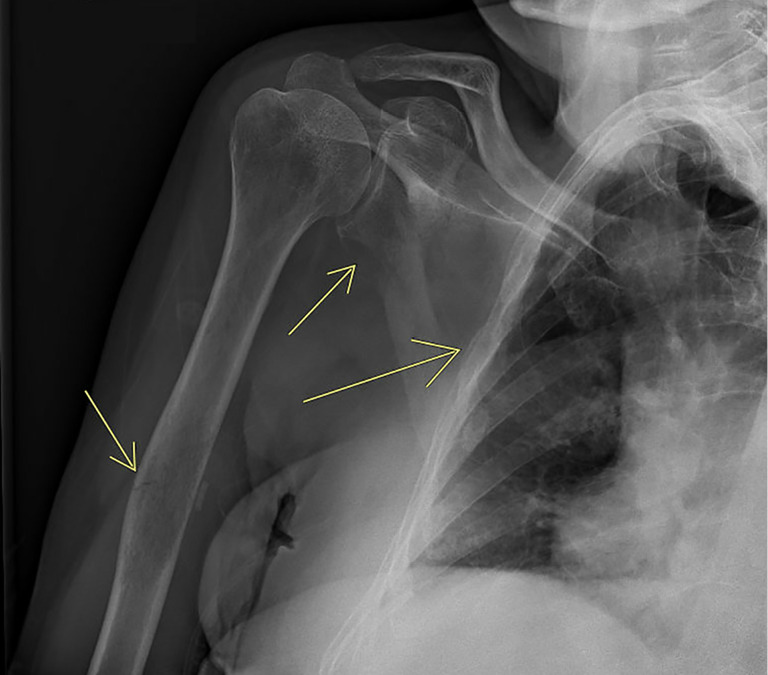

Background: Clonal hematopoiesis of indeterminate potential (CHIP) is characterized by genetic alterations associated with hematologic neoplasms, posing clinical challenges in managing concurrent hematological malignancies. CHIP may complicate the treatment landscape due to its potential to influence disease progression and treatment response. We report a 73-year-old male with multiple myeloma (MM) harboring a CHIP PPM1D mutation, elucidating the complexities and therapeutic considerations in such cases.

Case description: After four cycles of cyclophosphamide, bortezomib, and dexamethasone therapy, he achieved a partial response, followed by complete hematologic response (CR) post eight cycles of lenalidomide, dexamethasone, and bortezomib therapy. Despite this, upfront autologous hematopoietic stem cell transplantation (HSCT) was initially deemed unsuitable due to positive PPM1D CHIP status. HSCT proceeded after aggressive relapse with clonal evolution but yielded short-lived response. Following failure of >4 lines of therapy, he received chimeric antigen receptor T (CAR-T) cell therapy (ciltacabtagene autoleucel) for salvage. This approach successfully induced remission, which was maintained for 6 months.

Abstract Image